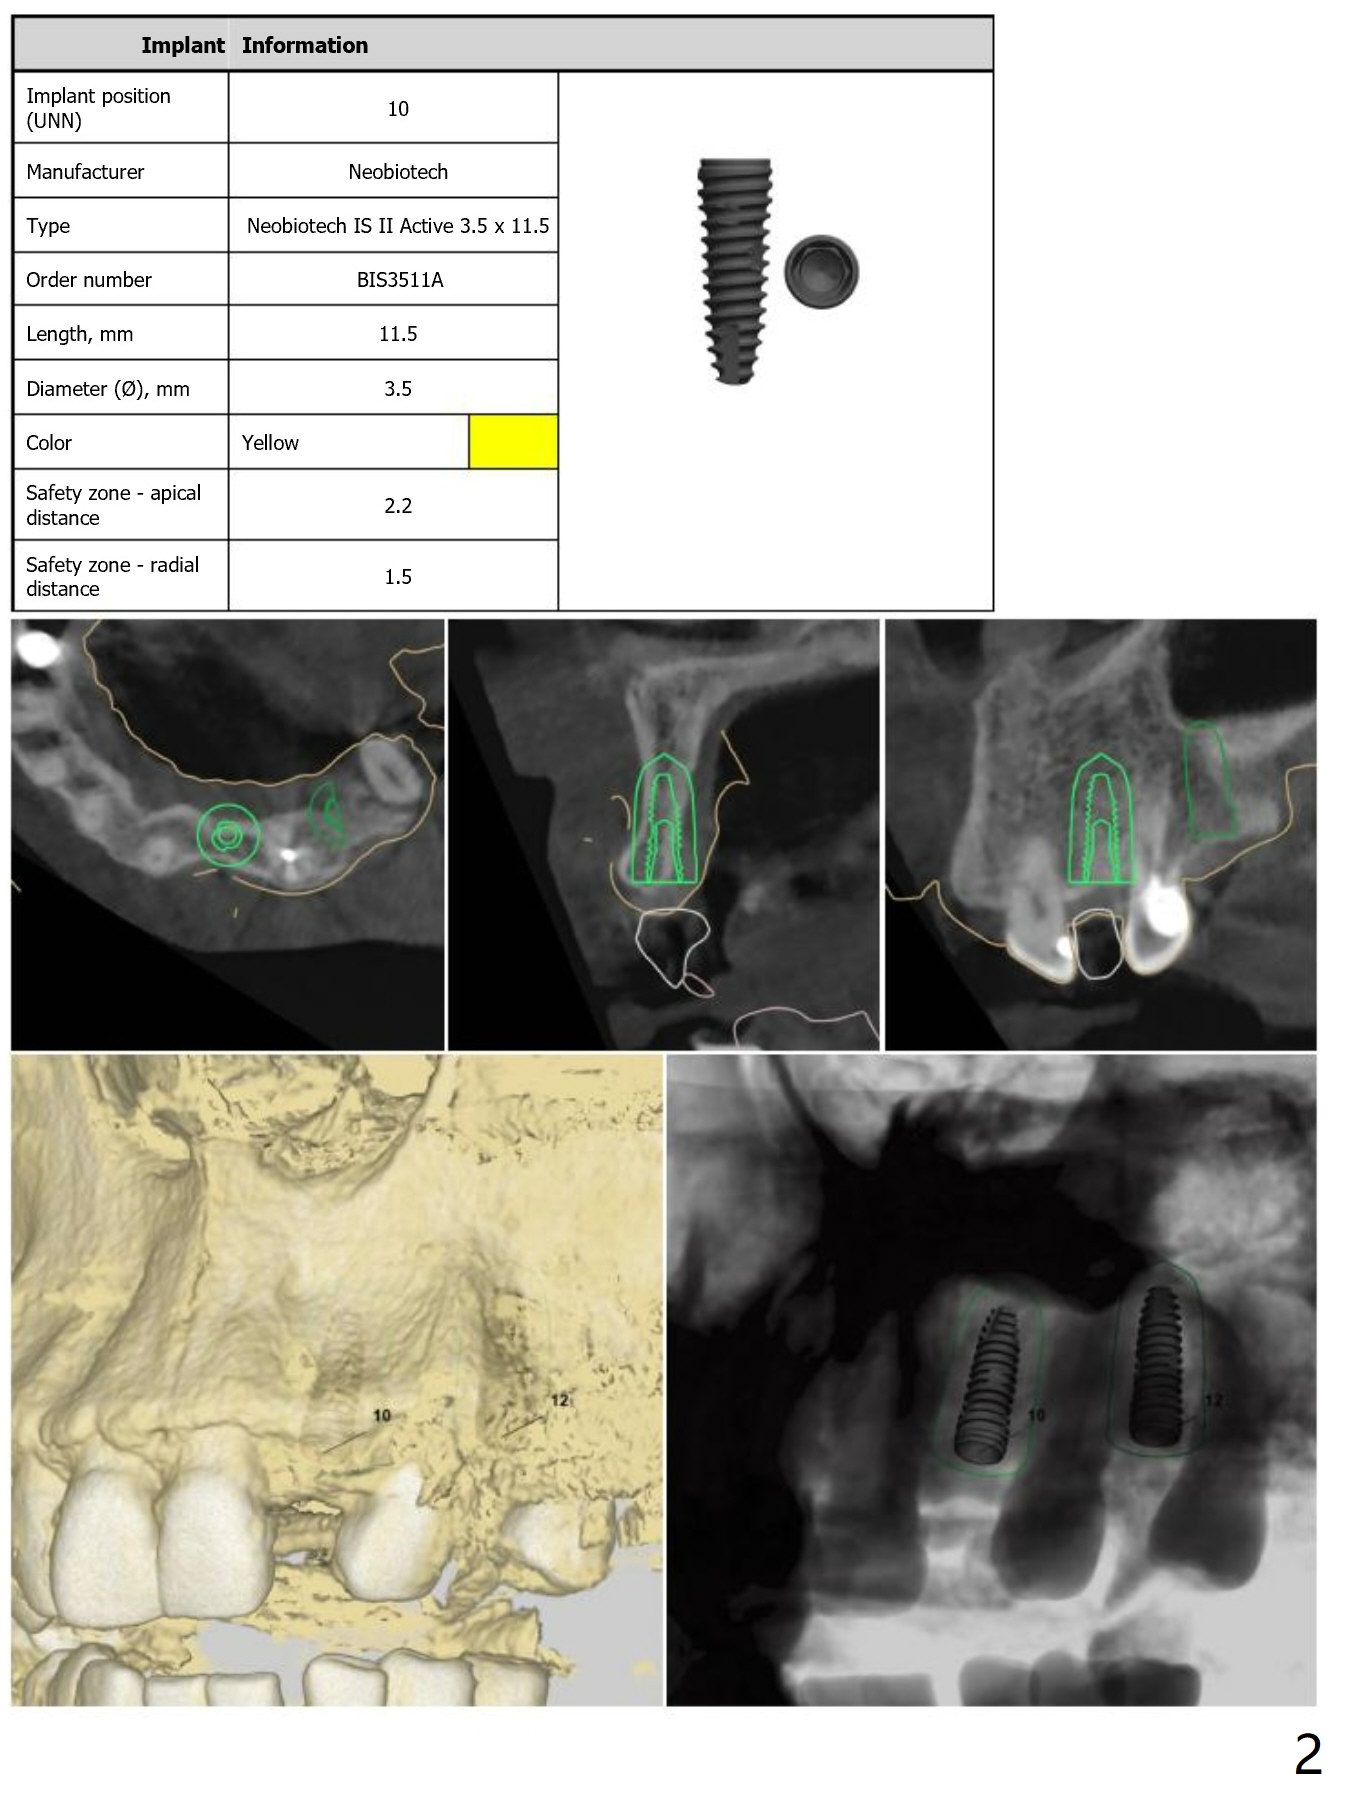

Guided 1-Piece Implant

Return to Upper Incisor Premolar Immediate Implant, Trajectory

Xin Wei, DDS, PhD, MS 1st edition 09/15/2018, last revision 09/15/2018